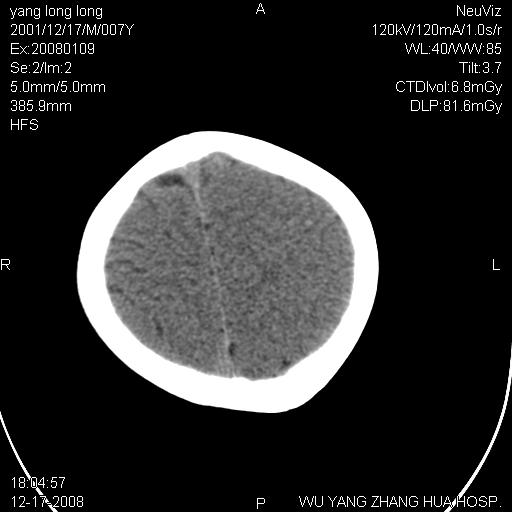

标题: PED1686:M7Y,头外伤,家人及自诉平时无任何不适。 [打印本页]

标题: PED1686:M7Y,头外伤,家人及自诉平时无任何不适。

考虑蛛网膜囊肿,请老师们看看多指导指导。

多考虑大枕大池。本例颅骨歪歪的,灶后枕骨似有膨胀征像(为蛛网膜囊肿征像),但整个左侧枕叶后方枕骨均有向后膨隆,所以暂不考虑蛛网膜囊肿。必要时随访